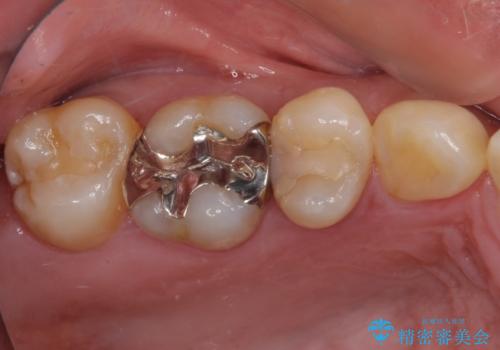

- 奥歯がしみて激痛が続くとのことで来院された患者様です。

診査の結果、不適合な銀歯の隙間からむし歯が進行しており、更には頬側、口蓋側ともに歯肉縁付近に強い知覚過敏症状が認められました。

健全歯質が多いため、インレーおよびむし歯を除去した上で知覚過敏を緩和させる処置を行うことが望ましいと判断されましたが、知覚過敏の症状が一向に改善されないため、全体をセラミッククラウンで補綴することとしました。